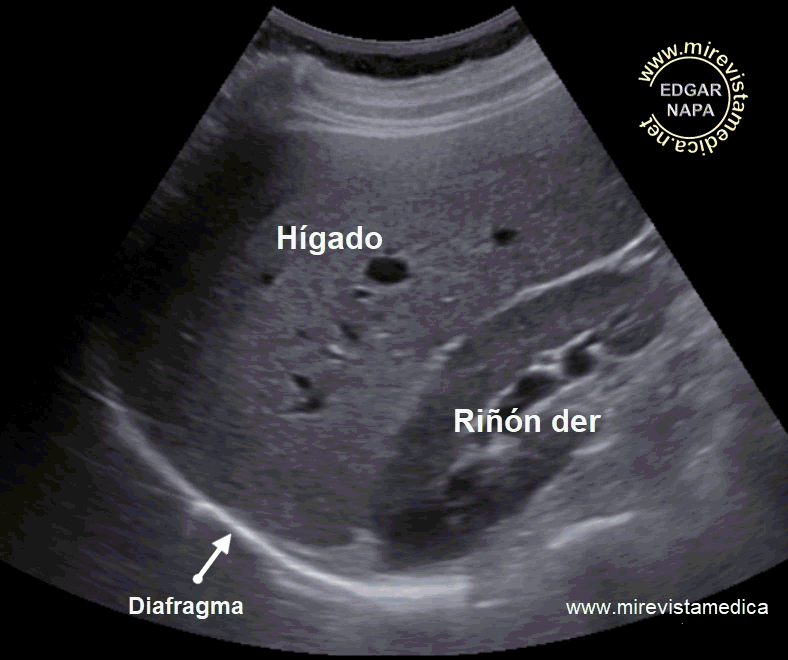

Localización : Situado en la parte superior derecha de la cavidad abdominal (espacio supramesocólico), debajo de la cúpula diafragmática, ocupando la casi totalidad del hipocondrio derecho.